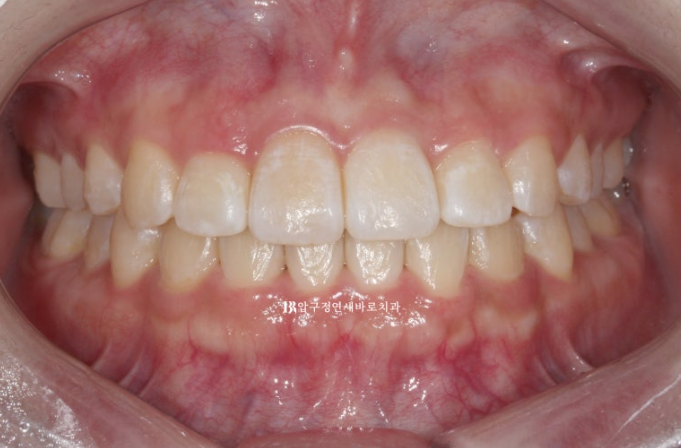

3개월에 걸쳐서 14개의 첫 세트 치료를 마무리 한 후 모습입니다.

앞니 뻗침이 많이 개선이 되었지만 앞니를 뒤로 조금 더 넣고 싶다는 환자분의 요구에 부응하여 추가장치 제작에 들어갑니다.

24.01

들려있던 일자로 내려오면서 치아가 처음보다 약간 길어보입니다.

웃을 때 치아가 일자로 딱 떨어지는 모양새가 보기에 가장 좋습니다.